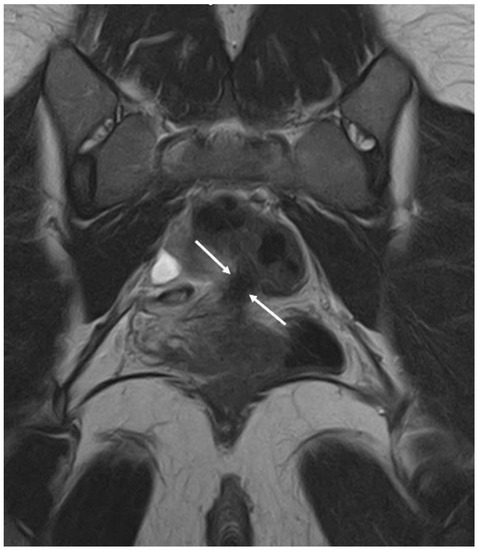

3.1. Ovarian Endometriosis

- Coutinho, A.; Bittencourt, L.K.; Pires, C.E.; Junqueira, F.; Lima, C.M.A.D.O.; Coutinho, E.; Domingues, M.A.; Domingues, R.C.; Marchiori, E. MR Imaging in Deep Pelvic Endometriosis: A Pictorial Essay. Radiographics 2011, 31, 549–567. [Google Scholar] [CrossRef] [PubMed]

- Lorusso, F.; Scioscia, M.; Rubini, D.; Ianora, A.A.S.; Scardigno, D.; Leuci, C.; De Ceglie, M.; Sardaro, A.; Lucarelli, N.; Scardapane, A. Magnetic resonance imaging for deep infiltrating endometriosis: Current concepts, imaging technique and key findings. Insights Imaging 2021, 12, 1–12. [Google Scholar] [CrossRef]

- Corwin, M.T.; Gerscovich, E.O.; Lamba, R.; Wilson, M.; McGahan, J.P. Differentiation of Ovarian Endometriomas from Hemorrhagic Cysts at MR Imaging: Utility of the T2 Dark Spot Sign. Radiology 2014, 271, 126–132. [Google Scholar] [CrossRef]

- Foti, P.V.; Farina, R.; Palmucci, S.; Vizzini, I.A.A.; Libertini, N.; Coronella, M.; Spadola, S.; Caltabiano, R.; Iraci, M.; Basile, A.; et al. Endometriosis: Clinical features, MR imaging findings and pathologic correlation. Insights Imaging 2018, 9, 149–172. [Google Scholar] [CrossRef]